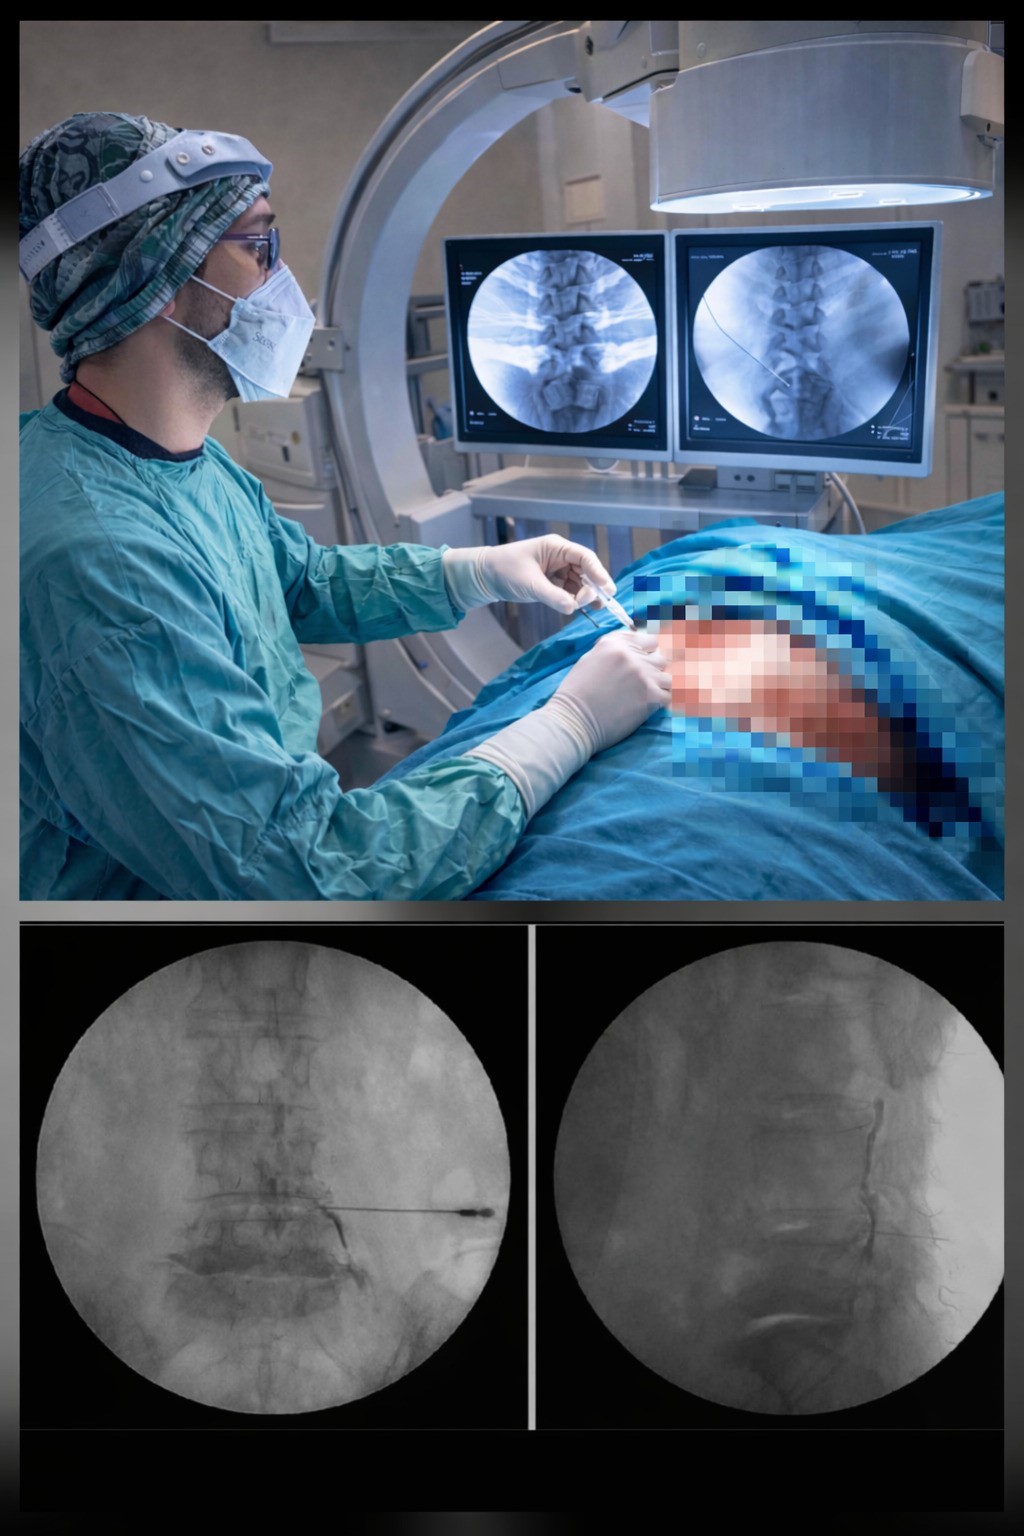

Ezine Devlet Hastanesi, bel fıtığı tedavisinde önemli bir yeniliğe imza attı. Ortopedi ve Travmatoloji Uzmanı Op. Dr. Ersen Türkmen tarafından hastanede ilk kez Transforaminal Epidural Steroid Enjeksiyonu (TFESI) yöntemi başarıyla uygulanmaya başlandı. Nokta atışı tedavisi olarak da bilinen bu modern yöntem, ameliyatsız çözüm sunarak hasta konforunu ve yaşam kalitesini belirgin şekilde artırıyor. Bel fıtığı, günlük yaşamı ciddi şekilde etkileyen, şiddetli bel ve bacak ağrılarıyla seyreden önemli bir sağlık sorunuyken uygulanan bu yeni yöntem sayesinde, hastalar artık cerrahiye gerek kalmadan etkili bir tedavi seçeneğine ulaşabiliyor. TFESI, fıtığın sinir köküne yaptığı baskının neden olduğu ağrı ve iltihabi süreci hedef alarak doğrudan problemli bölgeye tedavi uygulanmasını sağlıyor. Ameliyathane ortamında, görüntüleme eşliğinde yapılan bu işlem: küçük girişimsel, genel anestezi gerektirmez, süresi kısa, yatış gerektirmeyen bir işlem. Bu sayede hastalar günlük yaşamlarına çok kısa sürede dönerek iş gücü kaybı ve uzun istirahat süreçleri büyük ölçüde ortadan kalkıyor. Bu modern uygulama sonrası hastalarda: ağrı seviyesinde belirgin azalma, yürüme mesafesinde artış, uyku kalitesinde düzelme, günlük aktivitelerde rahatlama, psikolojik iyilik hâlinde artış gibi yaşam kalitesini doğrudan etkileyen olumlu sonuçlar görülüyor.

Ezine Devlet Hastanesi’nde ilk kez uygulanmaya başlanan bu yöntemle birlikte, bel fıtığı hastaları artık il merkezlerine sevk edilmeden, modern ve bilimsel tedaviye kendi ilçelerinde ulaşma imkânına kavuştu. Bu gelişme, hem hasta memnuniyetini artırmakta hem de bölge halkına kaliteli sağlık hizmeti sunulması açısından önemli bir adım.